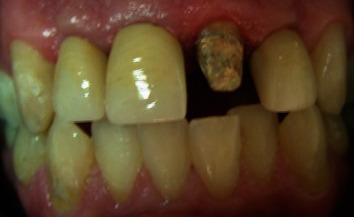

The management of teeth with deep caries, fracture, or perforation in the cervical third of the root is an integral part of dental practice. Orthodontic extrusion preserves the natural root system and may convert the tooth indicated for extraction into useful tooth with good prognosis and a low risk of failure. Orthodontic tooth eruption can be an alternative to treatment such as surgical crown lengthening, especially in esthetic areas, and provides more favorable conditions for prosthodontic coronal restorations by guaranteeing proper sealing and esthetics and preserving periodontal tissue health. The aim of this case report was to explain a multidisciplinary approach that successfully preserve and treat the teeth with subgingival carious lesion. This innovative method is cost-effective and can be easily done with the equipment available in any office.

对患有深龋、牙根折断或牙根颈部三分之一处穿孔的牙齿进行处理是牙科实践的一个重要组成部分。正畸牵引保留了天然的牙根系统,并且可以将原本需要拔除的牙齿转变为预后良好且失败风险低的可用牙齿。正畸牙齿萌出可以替代诸如外科冠延长术等治疗方法,特别是在美学区域,并且通过确保适当的封闭和美观以及保持牙周组织健康,为修复冠修复提供了更有利的条件。本病例报告的目的是阐述一种成功保留和治疗伴有龈下龋损牙齿的多学科方法。这种创新方法具有成本效益,并且使用任何诊所都具备的设备即可轻松完成。